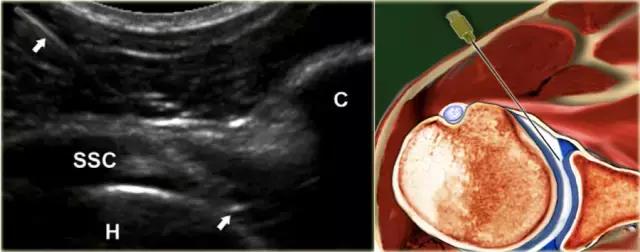

超声引导的跗骨窦的注射在右手侧与外侧入路。探头保持在冠状倾斜平面中。针沿着探头的长轴引入。

使用超声波可以容易地观察窦性骨壁。患者转向对侧,将待治疗的足以其内侧表面靠在桌面上,脚的外侧位于最上面。探头保持在关于脚的冠状平面中。

在跗骨窦被识别为跟骨的前处理和距骨颈之间的三角空间。针(箭头)的前端的锥形跗骨窦,这是由距骨(T)和跟骨(C)的边界内可以看到。